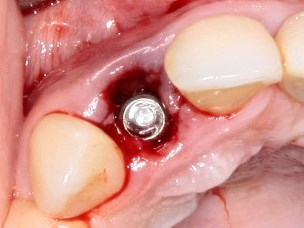

Немедленная имплантация — оптимальное решение в любой клинической ситуации